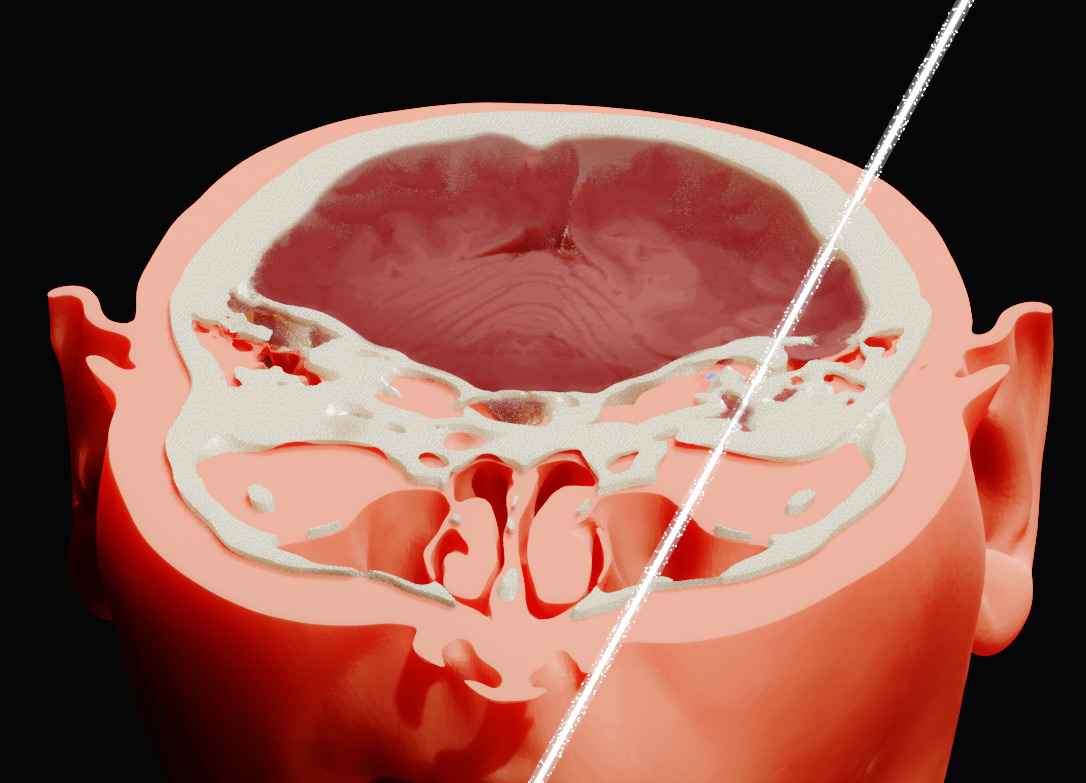

According to the authors of a new study, recreating the beam’s path through Bugorski’s skull was particularly challenging due to a lack of original images or medical documents. All they had to go on was a single, grainy photograph showing the approximate course of the ray through the physicist’s swollen head.

When creating a 3D rendering of the image, however, the authors noticed that the original photo is somewhat deceptive, as it appears to be a profile shot when in fact it depicts a slight rotation of Bugorski’s face. This enabled them to reconstruct the line of damage, which passes mostly through Bugorski’s temporal lobe, close to the point at which it meets the occipital lobe.

The reconstructed proton beam trajectory also crosses the bony labyrinth of Bugorski’s left ear, which makes sense given that he became deaf on this side after the incident. He also experienced numbness on the left side of his face, which the researchers say may be due to the beam damaging either the infraorbital nerve or the temporal bone, before exiting near his left nostril.